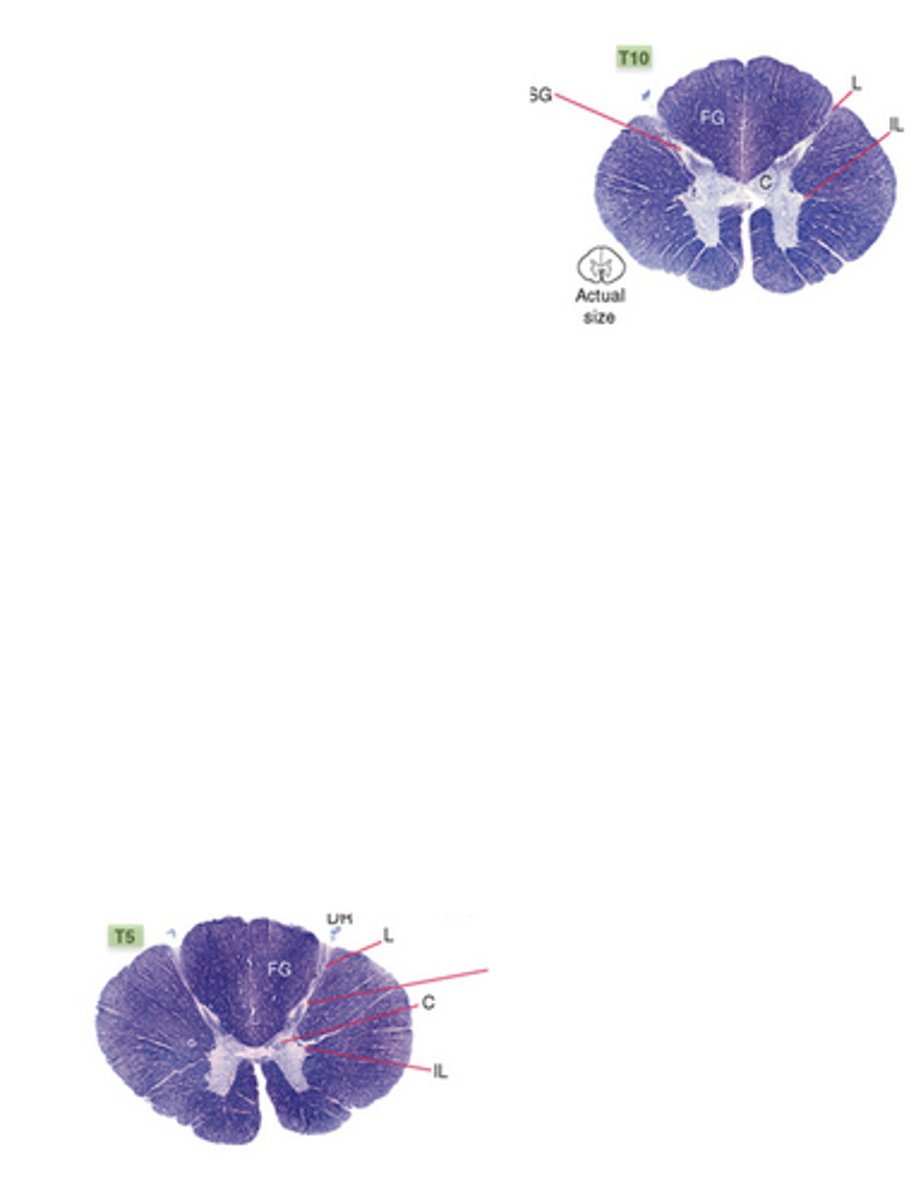

which division of the spinal cord is round, with small anterior and posterior horns, and lateral horns present?

thoracic

which division of the spinal cord is round, has less white matter than any other levels, has large anterior and posterior horns forming an enlargement throughout the entire division?

lumbar; lumbosacral enlargement from T11-S1